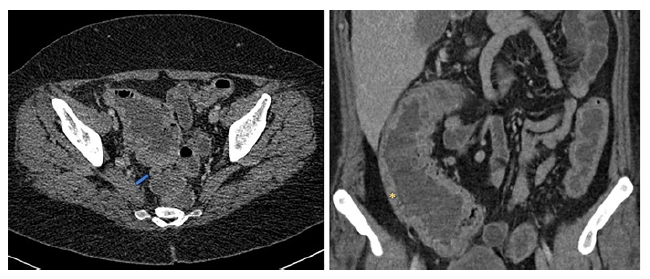

On examination at the Emergency Department, she was hemodynamically stable but exhibited tenderness in the right lower quadrant. Laboratory investigations revealed anaemia, elevated platelet count, and increased C-reactive protein (CRP) and procalcitonin (shown in Table 1). Given the significant right lower quadrant abdominal pain, a CT scan was performed, revealing thickening of the bowel wall in the ascending, transverse, and descending colon, with a slight thickening of the appendix, although without significant mesenteric fat hypertrophy (shown in Fig. 2). The surgical team assessed the patient and concluded that the presentation was atypical for appendicitis.

Fig. 2. CT scan at admission demonstrating a thickened appendix (left image, blue arrow) and a thickening of the bowel wall in the ascending colon (right image, yellow*).